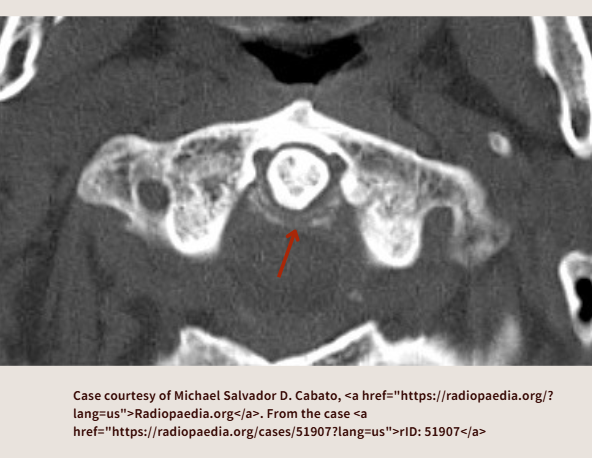

下のCT画像は横靭帯の石灰化です。(赤矢印は自分で追加)